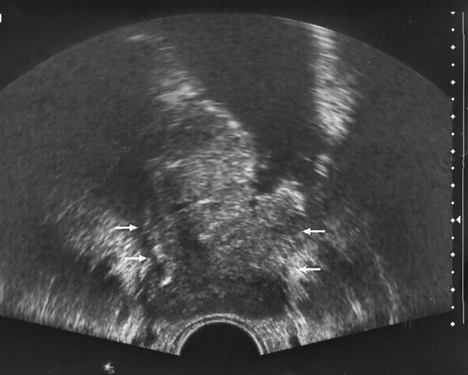

Рисунок 2. Рак мочевого пузыря, стадия T2b

УЗТ мочевого пузыря в поперечной плоскости. Опухоль располагается на правой боковой и задней стенках. Стрелками указано распространение процесса за пределы стенки органа и зона инфильтрации устья мочеточника. По левой боковой стенке — дивертикул